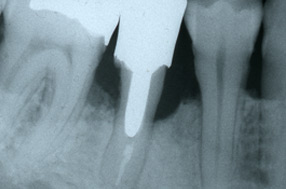

■歯周病治療例

歯周病の進行に伴う歯肉の

炎症と歯の移動が見られます。

歯周外科手術と同時に矯正で

歯周組織の再生と審美回復と

なりました。